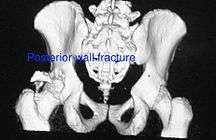

Use of CT scan with 3-D reconstruction of images has made understanding of these fractures easier.

Posterior wall fracture

This is the most common variety of fracture

Cause: Occurs due to dash board injury. When a person travelling in a vehicle involved in head-on collision, the force applied over the flexed knee travels along the femur bone to the head of femur breaking the posterior wall of the acetabulum. The head of the femur is dislocated outside the joint.

How to diagnose: Best seen in obturator oblique view

CT scan helps in identifying impaction of bone pieces and if there are pieces in the joint